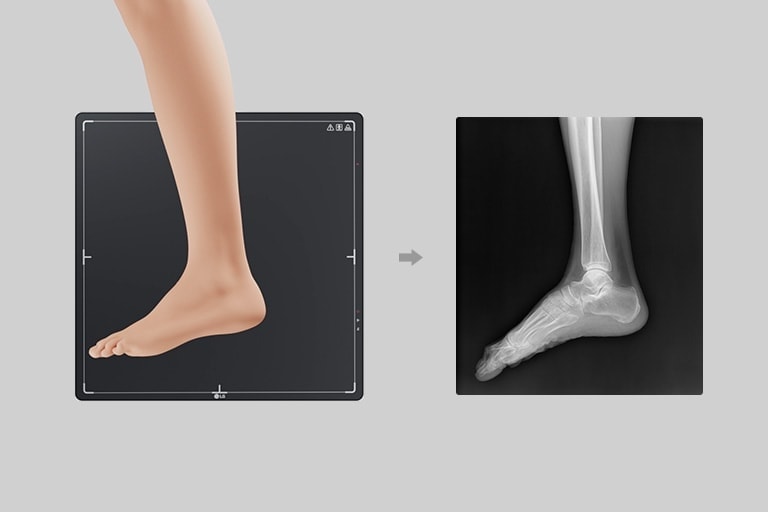

LG Digitaler Röntgendetektor mit a-Si TFT

TFT aus amorphem Silizium

Klare Bilder erhalten